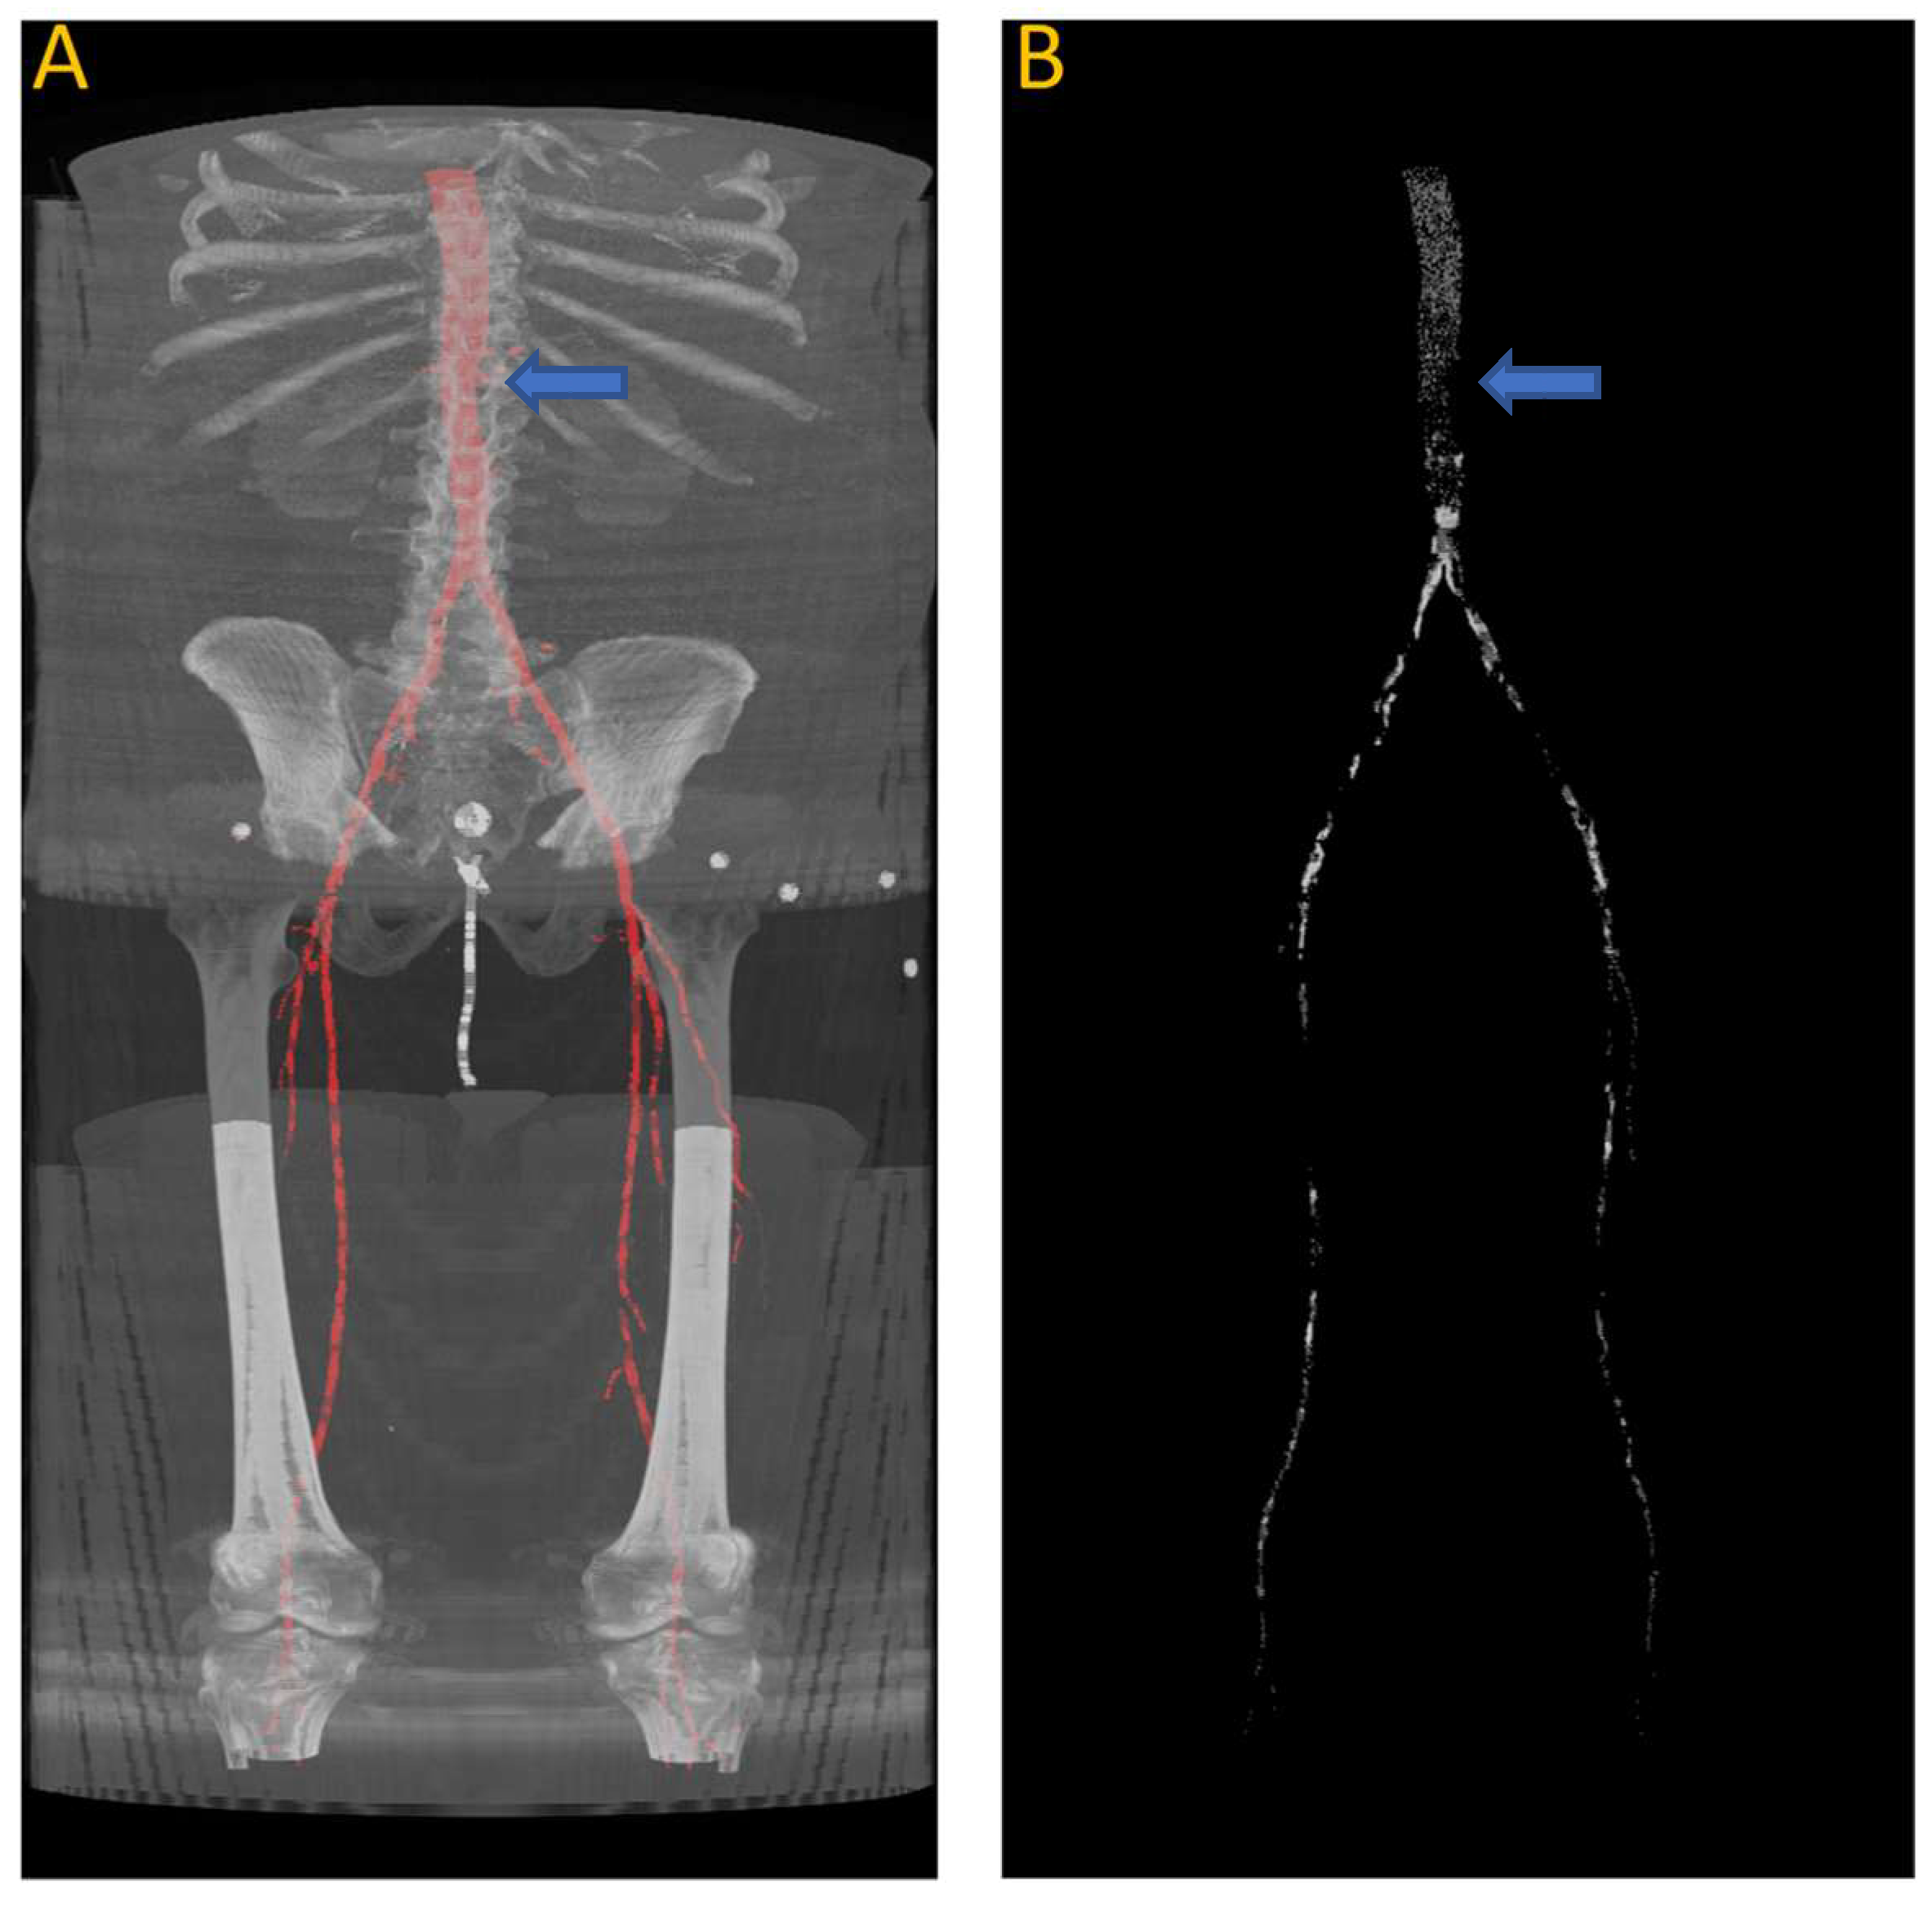

Figure 9 shows the results of the segmentation of the vascular system using the first model and calcification tracking within these arteries of the same patient analyzed in Figure 8. It is evident that this patient exhibits a high degree of arterial calcification, with a significant presence of calcified deposits. The manual calcification score on this patient is measured from slice 93 (left renal artery), indicated by the blue arrow in Figure 9, all the way to the patella. The manual calcification score is 7892, while the automatic is 7707, giving an Absolute Percentage Error (APE) score of 2.04%.

Figure 9.

(A) Automated artery segmentation. (B) Automated calcification tracking in arteries in a CT image for patient “J2” after intensity thresholding on (A). The blue arrow indicates the location of the left renal artery, which serves as the starting point for measuring the calcium score.